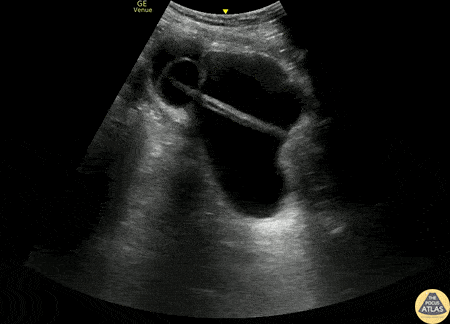

Renal/GU - Bladder Diverticulum

60s M with past medical history of BPH with chronic indwelling foley catheter was referred to the ED after his foley catheter was noted to be not draining properly after replacement in urology clinic. POCUS demonstrated the foley balloon and distal catheter in a large bladder diverticulum, with resulting urinary retention. Under real time guidance, the balloon was deflated, retracted, and re-inflated in the bladder, and the bladder diverticulum and bladder both decompressed appropriately. Molly Thiessen MD, Attending Physician, Denver Health Residency in Emergency Medicine